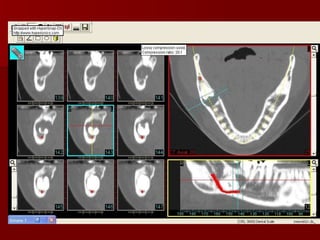

Imaging of Lingual Nerve Injuries CT

Imaging of LingualNerve Injuries CT